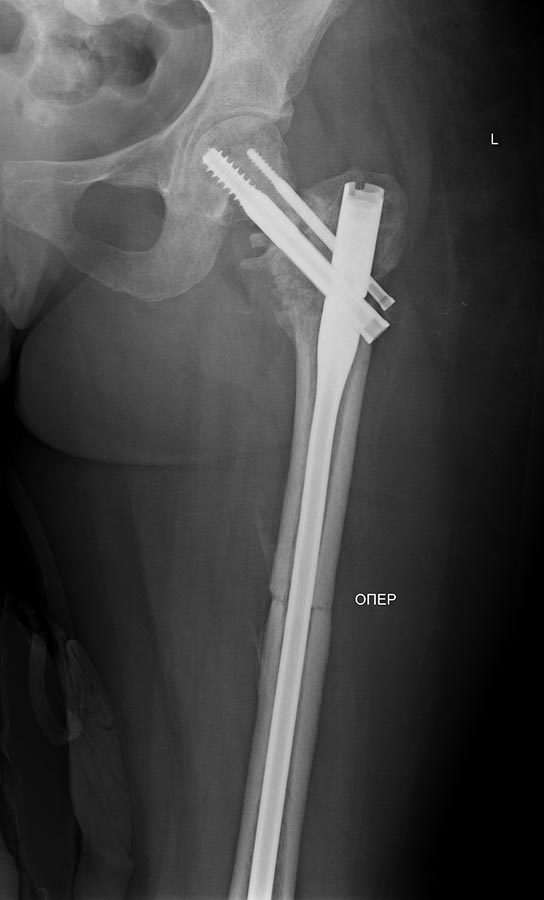

Продолжение истории, начало см. http://weborto.net/forum/1370513039/.Сегодня сделали левое бедро. Сделана аналогичная чрескожная вальгизирующая остеотомия, закрытый интрамедуллярный остеосинтез Affixus. Длинным, с учетом еще и бывшего диафизарного перелома. Были какие-то мысли насчет пластики дефекта шейки - решили воздержаться.